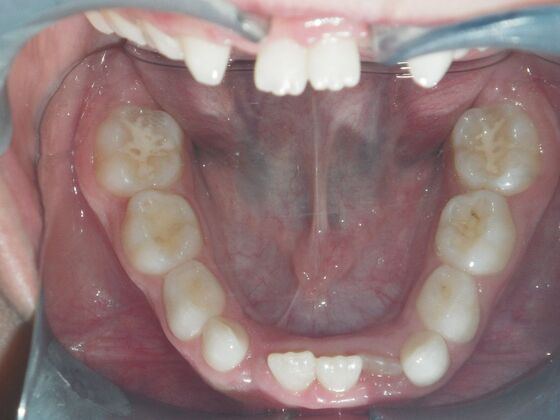

Orthodontic treatment in Phases: Case 8

Dylan presented with a functional crossbite in which we used removable expansion appliances for 12 months, followed by bracketing of upper and lower teeth including primary ones to gain alittle more expansion, allowed to wear retainers for 6 months and then followed closely with 6 month ortho recalls and began Phase 2 treatment within 24 months and finished his ortho treatment.